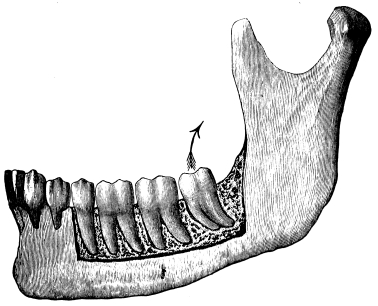

A correct acquaintance with the disposition of the alveoli of the teeth is of importance for skilful and successful operating. Fig. 15 gives a general idea of the appearance of the alveoli, but it is needless to say that a full knowledge can only be really obtained by a careful study of the bones themselves; by this means, too, some idea of the strength of different portions of the alveolar borders can be obtained—a matter of some moment when applying force in the process of removing a tooth from its socket. The points to be specially noted in the maxilla are the thinness of the outer alveolar wall as compared with the inner, the prominence of the canine socket, and the cancellous character of the bone in the region of the third molar. In the mandible the outer alveolar border will be seen to be thinner than the inner, with the exception of that portion in the region of the{13}

third, and often of the second molar; another fact worthy of attention is that at the posterior portion{14} of the socket of the third molar the bone is moderately dense.